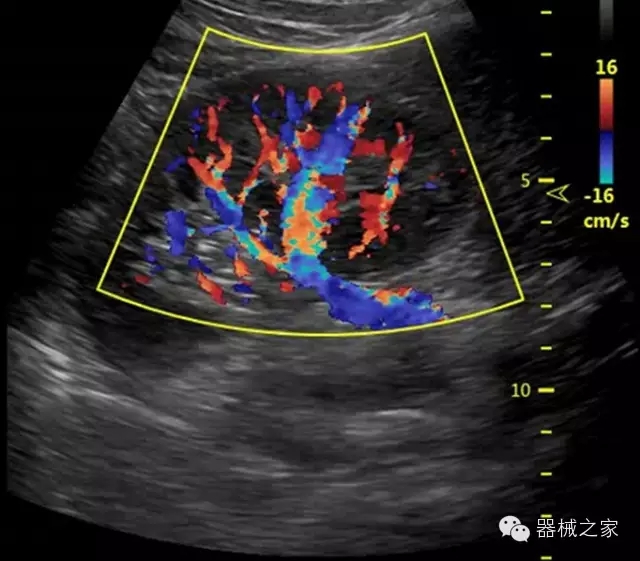

臨床圖片賞析

產(chǎn)品特點

·獨有的RF平臺提高微小細(xì)節(jié)顯示、圖像對比度和邊界清晰度;

·特有的XCEN探頭,超寬的帶寬,表現(xiàn)更高分辨率和對比度;

·單晶純凈波探頭提供更佳的穿透力和彩色敏感度;

·完整的3D/4D臨床應(yīng)用,STIC, MCUT 和Auto NT等滿足產(chǎn)科所有應(yīng)用;

·更高的HQ羊膜腔鏡成像技術(shù)精細(xì)觀察每一個暗區(qū)細(xì)節(jié);

·智能的觸摸屏界面,能任意角度方位旋轉(zhuǎn)3D圖像,以及注釋快速標(biāo)記,提供直觀與便捷的操作,提高了工作效率;

介入室/手術(shù)室

·Needle Enhancement 穿刺增強技術(shù),清晰顯示穿刺針尖,定位目標(biāo)精確穿刺;

·智能的聲控功能,以及全屏顯示真正意義上解決醫(yī)生術(shù)中應(yīng)用;

Xcen探頭技術(shù)

·獨有的Xcen高頻18MHz探頭,使微小病灶的顯示成為現(xiàn)實,為臨床提供了更廣泛的臨床應(yīng)用;

·Xcen超寬頻帶探頭技術(shù)比常規(guī)探頭頻寬提高了30%,具有更廣泛的臨床應(yīng)用,更高的頻率讓我們獲得了更好的細(xì)微分辨率和對比度的圖像;

肌骨理療

·智能感知組織特異性的VTissue技術(shù),結(jié)合特有高達(dá)22MHzXcen線陣探頭, 以及獨有敏感的RF射頻血流提供了優(yōu)異臨床圖像;

·智能的教學(xué)操作流程提供全面及專業(yè)的操作步驟指導(dǎo),便捷藍(lán)牙傳輸保障信息流暢;

便捷傳輸功能

·藍(lán)牙傳輸/ WIFI 郵件/ 移動網(wǎng)絡(luò)/ DICOM;

·ICU/CCU;

·飛依諾特有心臟純凈波探頭提供更好的穿透力和彩色敏感度,以及結(jié)合TView梯形拓展改善困難病人深部組織成像;

·獨有RF敏感血流使得心臟血流完美呈現(xiàn);